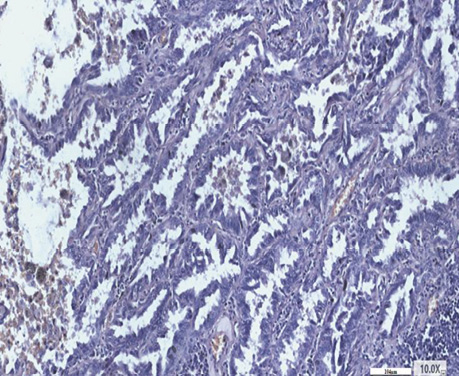

Спеціальне детальне дослідження серійних зрізів усіх препаратів від 30 хворих дозволило визначити ділянки, де ріст РЛ відмічався в альвеолах з характерним напрямком росту від базальної мембрани до центру, в якому часто виявлялися некротичні маси з пухлинними клітинами з усіма характерними морфологічними ознаками БАРЛ. У структурі плоскоклітинного раку виявлений солідний ріст пухлини, який заповнює альвеоли. Чітко прослідковуються окремі альвеоли, заповнені пухлинними клітинами. У таких ділянках можна фіксувати міжальвеолярні перетинки, іноді з еритроцитами в них (рис. 1, 2). Серед альвеол з пухлинним ростом відзначаються такі, що уражені раком наполовину, а також деякі альвеоли без ураження РЛ з типічним вмістом всередині альвеол пневмоцитів І типу (АТІ), макрофагів і лейкоцитів. Поруч з тим визначаються типові структури плоскоклітинного раку з різним ступенем диференціювання, ділянками фіброзу між альвеолами. Зазначені різні компоненти гістологічних ділянок у складі плоскоклітинного раку створюють складності в поточній гістологічній діагностиці при уточненні типу РЛ і ступеня його диференціювання.

Рис. 1. Плоскоклітинний рак. Ріст в альвеолах. Гематоксилін і еозин. Збільшення ×200